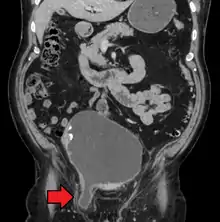

A physician may diagnose an inguinal hernia, as well as the type, from medical history and physical examination.[20] For confirmation or in uncertain cases, medical ultrasonography is the first choice of imaging, because it can both detect the hernia and evaluate its changes with for example pressure, standing and Valsalva maneuver.[21]

When assessed by ultrasound or cross sectional imaging with CT or MRI, the major differential in diagnosing indirect inguinal hernias is differentiation from spermatic cord lipomas, as both can contain only fat and extend along the inguinal canal into the scrotum.[22]

On axial CT, lipomas originate inferior or lateral to the cord, and are located inside the cremaster muscle, while inguinal hernias lie anteromedial to the cord and are not intramuscular. Large lipomas may appear nearly indistinguishable as the fat engulfs anatomic boundaries, but they do not change position with coughing or straining.[22]